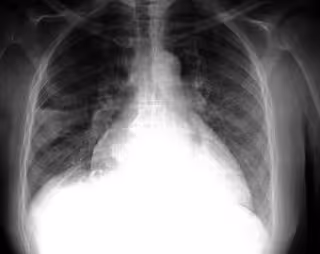

FLICKR/PULMONARY PATHOLOGY/CC BY-SA 2.0 - Archivo

La fibrosis pulmonar se asocia con una mayor formación de tejido conectivo en los pulmones, lo que produce cicatrización del tejido pulmonar funcional. Esto conduce a una disminución en la superficie interna de los alvéolos extremadamente finos y la extensibilidad de los pulmones, que a su vez impide la entrada de oxígeno y la liberación de dióxido de carbono. El resultado es una función pulmonar deteriorada.